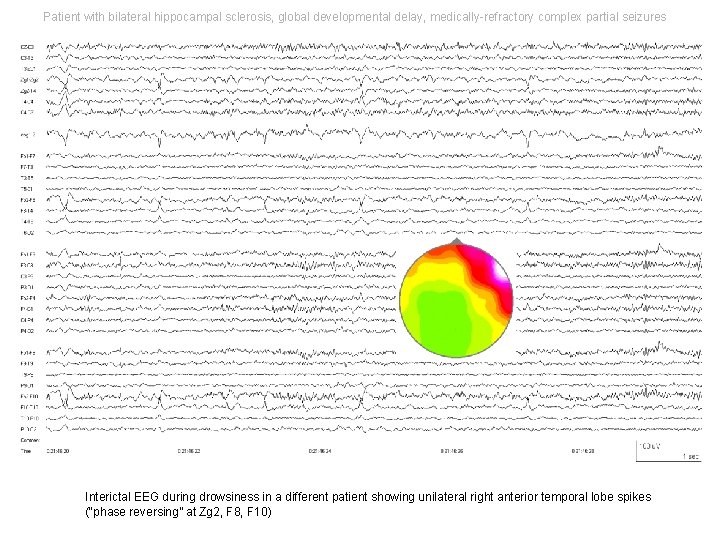

Patient with bilateral hippocampal sclerosis, global developmental delay, medically-refractory complex partial seizures Interictal EEG during drowsiness in a different patient showing unilateral right anterior temporal lobe spikes (“phase reversing” at Zg 2, F 8, F 10)